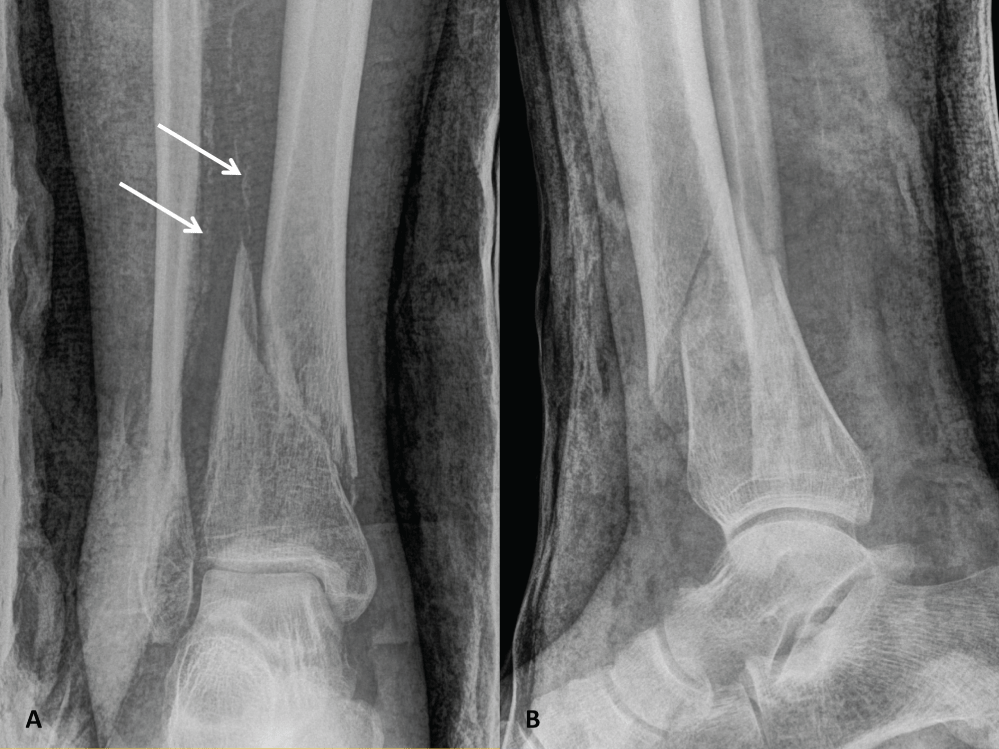

The use of this approach is exemplified with the case of a 65-year-old male, smoker and chronic alcohol abuser, who sustained a low-energy closed distal diaphyseal tibio-peroneal fracture on the right side (AO/OTA type 42-B2; Figure 1). Right unilateral absent pedal pulse was noted upon admission, with normal distal skin perfusion and preserved DPN function. On the contralateral non-injured extremity, pedal pulse was felt on palpation, distal skin perfusion was normal, as well as DPN function. Posterior tibial pulses were present bilaterally and compartments of the leg were soft and non-tender. Diffuse calcifications of all infra-popliteal vessels were visible on plain radiographic views (Figure 1). The absent pedal pulse motivated a Computed Tomography Angiography (CTA) that confirmed diffuse atherosclerotic disease as well as ATA entrapment at the fracture gap: vascular flow was interrupted at a kink over the bony prominences of the fracture and distal reperfusion was noted from functional collaterals (Figure 2).

Figure 1: Plain anteroposterior (A) and lateral (B) radiographic views showing a right distal spiroid diaphyseal tibia fracture (AO/OTA type 42-B2) associated with a comminuted distal fibula fracture. Arrows indicate diffuse calcifications of infra-popliteal vessels. View Figure 1

Postoperative radiographs showed adequate fracture reduction. Wound healing occurred uneventfully. The patient was full weight bearing at 12 weeks and radiographs confirmed ongoing bone union at 16 weeks (Figure 5). At time of last follow-up, at 12 months, the patient was pain-free, active and ambulating, and radiographs showed complete bone union (Figure 6). Pedal pulse was present throughout follow-up and the patient had no complaints suggestive of vascular insufficiency of the affected limb. DPN function was preserved. Ankle range of motion reached a flexion-extension of 45-0-5° at last follow-up after intensive physiotherapy.

Figure 5: Plain anteroposterior (A) and lateral (B) radiographic views 16 weeks after definitive osteosynthesis demonstrating ongoing fracture consolidation. View Figure 5

Figure 6: Plain anteroposterior (A) and lateral (B) radiographic views 1 year after osteosynthesis showing complete fracture consolidation. View Figure 6